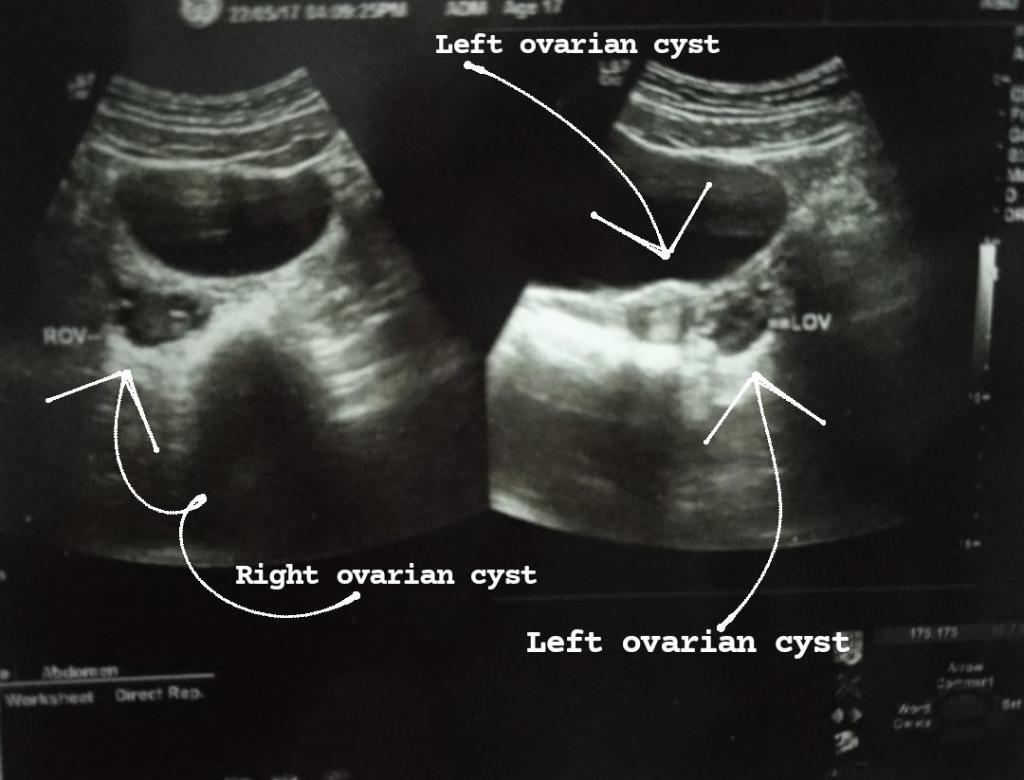

Now irregular periods was a big deal as it had been 3 years I got my periods and i should have got i right till now like every month on time. So I consulted with a Gynecologist, she told me to test for my thyroid and get sonography diagnosis to check if I have cysts. So thyroid was negative and PCOS test was positive.

In 2015 i was diagnosed with PCOS. Me and my parents were new to this word. My doctor suggested me to loose weight and didn’t gave any prescriptions as she said i was too young to have medicine treatment.